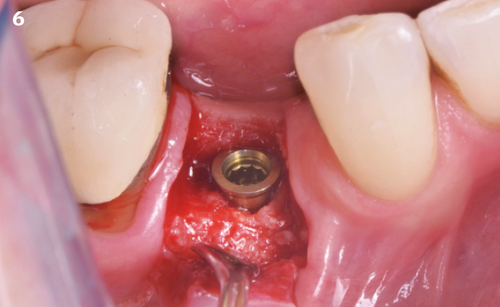

"After the extraction, I realized that the buccal wall was missing and I had to leave the membrane exposed. The regenerative potential of the site could be poor, so I decided to boost the biomaterials’ effect with polynucleotides and hyaluronic acid."

The Situation

The patient (45 years old, female, non-smoker, no previous pathologies) is referred for extraction of tooth 45 and immediate implant placement. The site showed an increased probing depth and a marked bone loss.